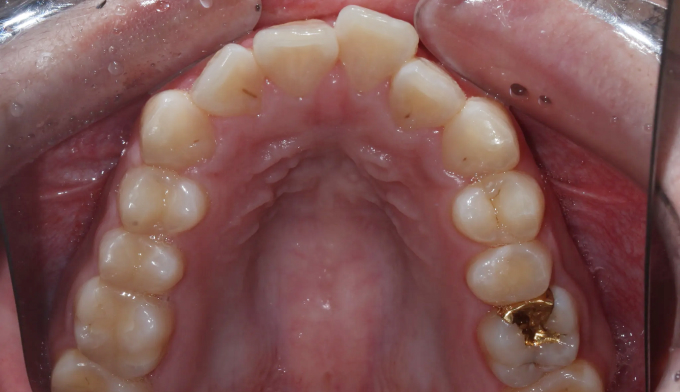

돌출입과 불규칙한 앞니를 가지고 있습니다. 그리고 아래쪽에 ‘임플란트’가 있습니다.

임플란트는 뼈와 강력히 결합되어 있기 때문에 교정치료로 절대 움직일 수 없습니다. 따라서 해당 부위는 절대 교정치료로 움직일 수 없다는 제한점이 있는 상태에서 교정치료를 진행하게 되었습니다.

돌출입을 해소하고 앞니를 가지런하게 만들기 위한 공간을 만드는 과정중에는 저 임플란트를 꼭 제거해야 했으나, 최대한 발치 없이 교정을 진행하였습니다.

후방이동이 불가하므로 악궁확장을 통하여 공간확보를 시도하였고, 동시에 돌출감도 해소되었습니다.

최종적으로 임플란트의 존재때문에 중심선을 맞추지는 못했으나 환자분은 너무 만족해하셨습니다.

임플란트가 있다고 무조건 교정을 못하는것은 아닙니다.

총 치료기간은 14개월 소요되었습니다.